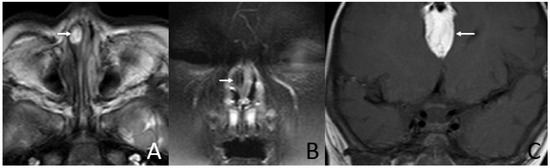

Figure 3. MRI of a 6-month-old and 18-day-old girl presenting shortly after birth with nasal obstruction. (A) Axial T2-weighted MRI shows a sausage-like mass (arrow) in the right nasal vestibule and nasal limen that is mainly high-signal with linear low-signal inside. (B) Coronal T2W-SPIR MRI shows the hyperintensity component of the mass suppressed (arrow). (C) Coronal T1-weighted MRI shows an irregular mass (arrow) containing fat in the intracranial midline that mainly has a high-signal with irregular linear low-signal inside.

In addition, three (21.4%) cases presented with irregular shapes the MRI or CT findings that were atypical. One case presented with a sausage-like mass in the right nasal vestibule and nasal limen that was mainly high-signal with multiple filament-like low signals inside on T1-weighted and T2-weighted MRI (Figure 3). One case presented with a multilayered circumferential mass in the left parapharyngeal space that was soft tissue, lipid, fibrous capsule, and soft tissue intense from inside to outside, and the mass extended to the left external auditory canal and middle ear (Figure 4). One case presented with irregular fat and soft tissue density mass originating from the back side of the left soft palate (Figure 5).

Six (42.9%) patients had other abnormalities. Five of them were incidental findings within the imaging scope of their investigations and one was in the other area. One infant had ossicular chain disruption showing the absence of the left stapes head and part of stapes arch (Figure 6), one had a cystic lesion of liver by abdomen ultrasound, one had frontal midline lipoma (Figure 3), one had a cleft palate (Figure 1) and pectus excavatum, one had a right first branchial fistula, and one had a cleft palate and ameloblastic fibro-odontoma of the mandible as well as highly suspicious ectopic teeth and the remnant of craniopharyngeal canal development (Figure 5).

Hairy polyps are not definitively associated with any syndromic disorder but have been reported to be associated with other congenital abnormalities such as cleft palate, uvula dysplasia, auricular deformities [18] such as microtia and low-set ears, ankyloglossia, facial hemihypertrophy, hypospadias, left carotid artery atresia, osteopetrosis [19], bifurcation of the tongue, and branchial arch anomalies [20,21]. Of particular importance is that they have been described to occur more frequently in patients with first or second branchial arch anomalies [22]. In rare cases, hairy polyps have been noted to occur with hypothalamic neuronal hamartoma [12] and polydactyly [16]. Neurological complications may occur secondary to vascular compression ischemia. In this paper, except for cleft palate and the first branchial fistula, other associated abnormalities, such as ossicular chain disruption, ameloblastic fibro-odontoma of the mandible, frontal midline lipoma, pectus excavatum, highly suspicious ectopic teeth, and remnants of craniopharyngeal canal development, have not been reported before. The associated abnormalities may be misdiagnosed at an initial visit if the imaging examination was not performed.